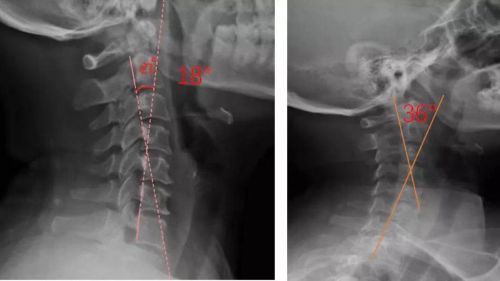

患者適配前后側(cè)位X光,佩戴前18°,適配后36°

對于頸椎病患者,合理設(shè)計的頸椎枕,能夠緊密適合頸椎,矯正頸椎生理曲度;再根據(jù)頸椎曲度改善情況,隨時間慢慢調(diào)整3D打印頸椎枕曲度,使變直的頸椎逐漸形成正常的生理曲度,改善頸肩痛的癥狀。